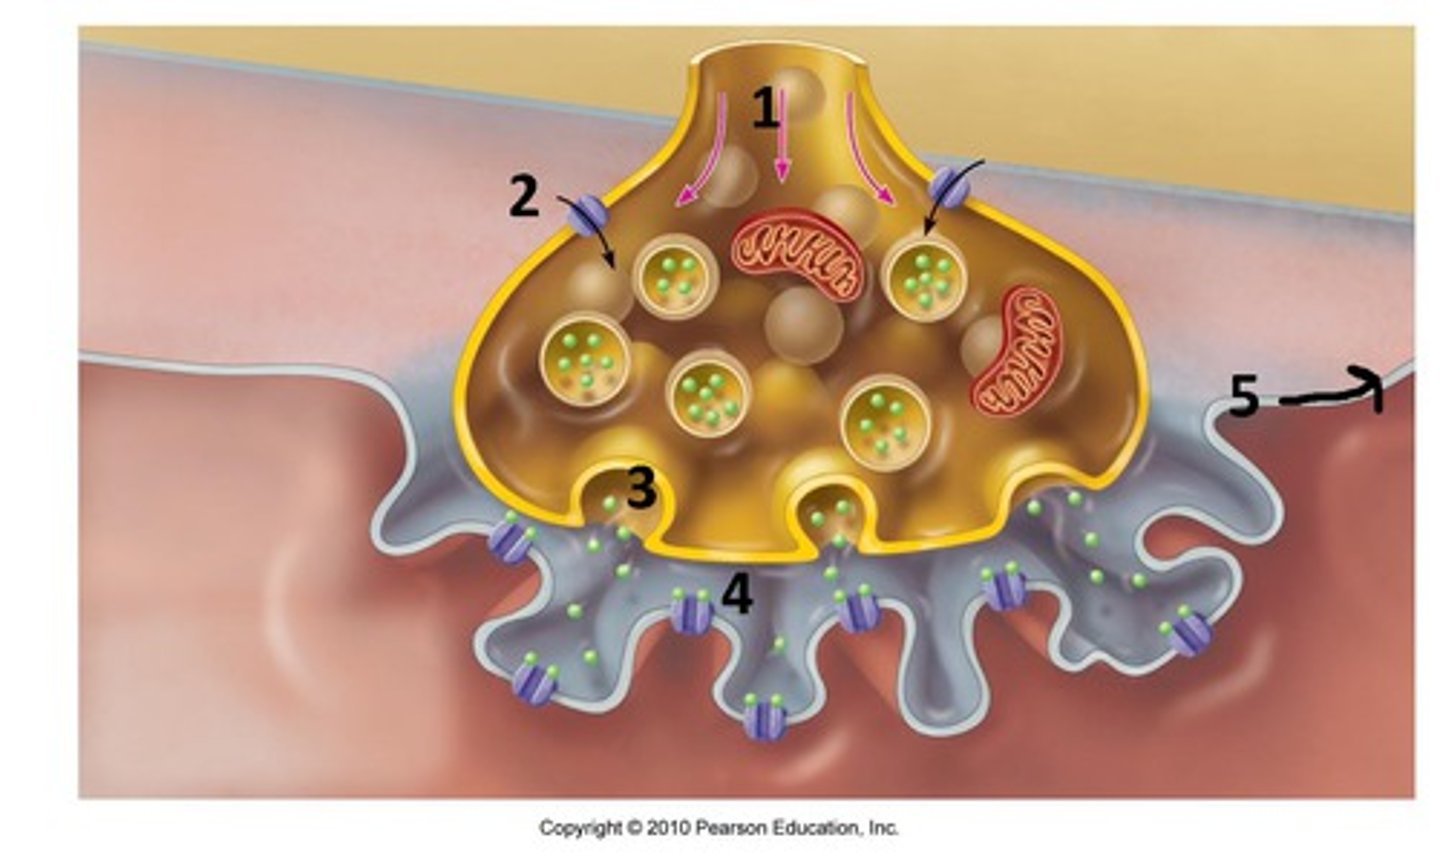

Action potential

a neural impulse (brief electrical charge) when a neuron sends information down an axon

Reuptake

reabsorption of a neurotransmitter by the sending neuron after it completes its work

Neural transmission

electrochemical communication within and between neurons and the final destination

Reuptake inhibitors

drugs that interfere with the reabsorption of neurotransmitters in the synapse so that a greater amount remains in the synapse